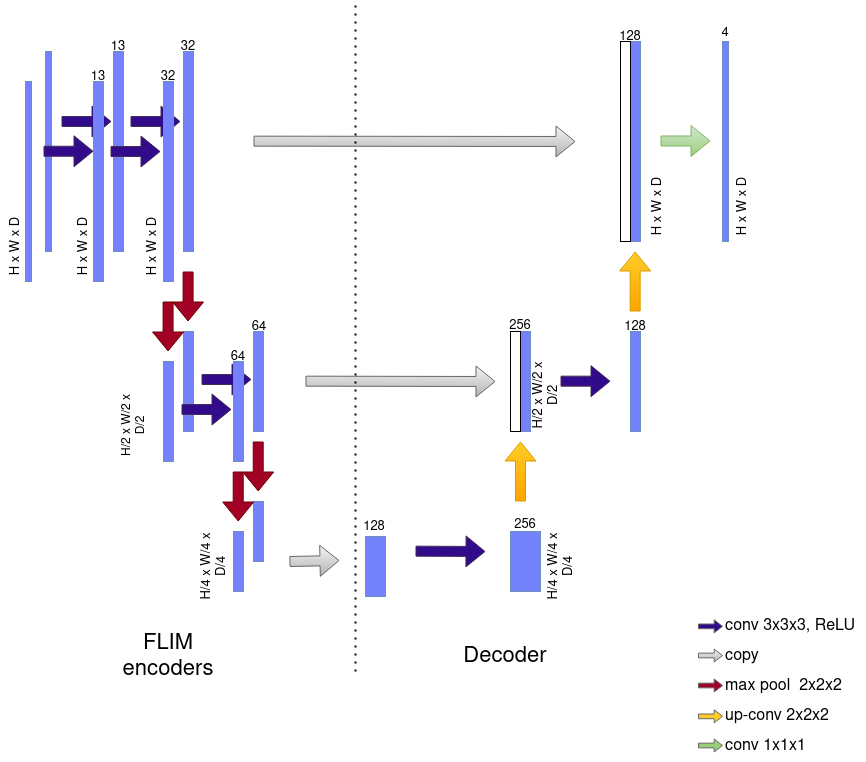

This section presents the experimental setup to validate MS-FLIM. We built a shallow U-shaped encoder-decoder network (Figure 4), named sU-Net, for GBM tumor segmentation into three regions: ET, NC, and Whole Tumor (WT). The literature usually reports the segmentation effectiveness for these three regions, assuming that . We used DICE (DSC) to measure effectiveness. We also compared the sU-Net-based methods with two SOTA baselines on two datasets.

|

The sU-Net architecture (Figure 4) consists of two encoders, one for T1Gd and the other for FLAIR images, with three convolutional layers each. Skip connections concatenate the output feature block, before each stridden pooling operation, with the output of a decoder’s layer after the transposed convolution. The skip connections provide fine-grained segmentation, and in the final layer, a convolution with kernels generates four channels, one for the background and one for each label (ED, ET, NC).